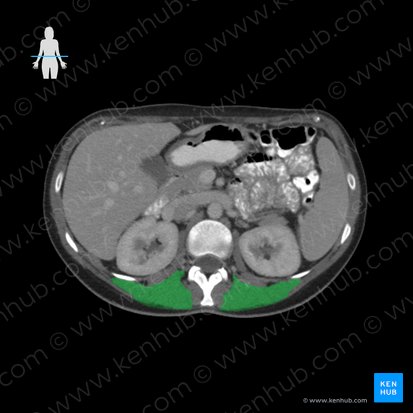

Die Auswertung der Strukturen auf einer CT-Aufnahme erfolgt normalerweise von lateral nach medial, beziehungsweise von außen nach innen. Bei der Befundung des Abdomens sollten wir mit der äußersten Schicht beginnen, die als feine hellgraue Kontur zu erkennen ist. Sie stellt die Haut dar. Darunter liegt das subkutane Fettgewebe, welches als schwarze Schicht zu sehen ist. Medial dieser Strukturen befinden sich die beiden Hauptmuskelgruppen der Bauchwand: Die anterolateralen und die posterioren Bauchwandmuskeln. Im anterioren Bereich des CT-Schnitts ist die anterolaterale Muskelloge zu erkennen, in der sich folgende Muskeln befinden: Der Musculus obliquus externus abdominis, der Musculus obliquus internus abdominis und der Musculus transversus abdominis. In ihrer unmittelbaren Umgebung befinden sich auch der Musculus rectus abdominis und die Rektusscheide. Im posterioren Abschnitt der CT-Aufnahme befinden sich die posterioren Bauchwandmuskeln. Zu diesen gehören der Musculus latissimus dorsi, der Musculus psoas major, der Musculus iliacus, der Musculus erector spinae, der Musculus quadratus lumborum und der Musculus psoas minor. Zwischen den Rückenmuskeln stechen die weißen (hyperdensen) Lendenwirbel hervor. Bei einer intakten Bauchwand sieht die äußere Linie des Abdomens unversehrt und ebenmäßig aus.